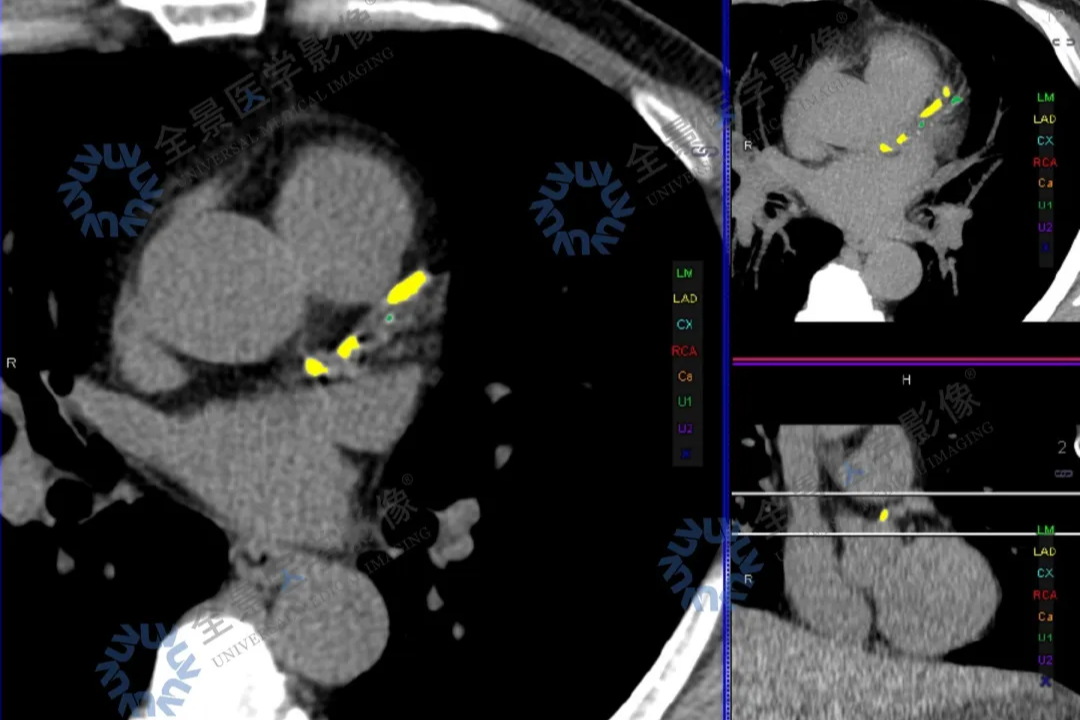

「牵一发而动全身」—以为是肺的事,PET/CT 揭秘—全身淋巴瘤